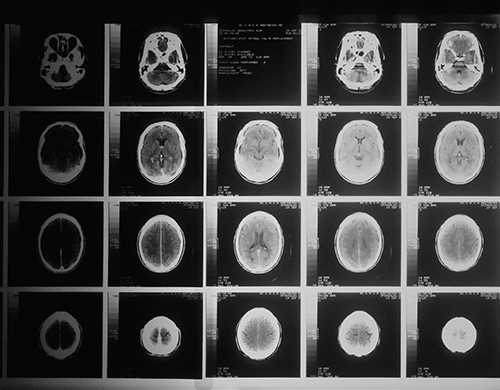

- Your 3-monthly MRI scans would be used along with a single CT scan to plan your treatment; this ensures you have minimal disruption to your therapeutic journey

- Requires recent imaging and pathology reports

- Eligibility is based on pre-screening criteria (e.g. concurrent health conditions, brain scan analysis and blood results etc.)